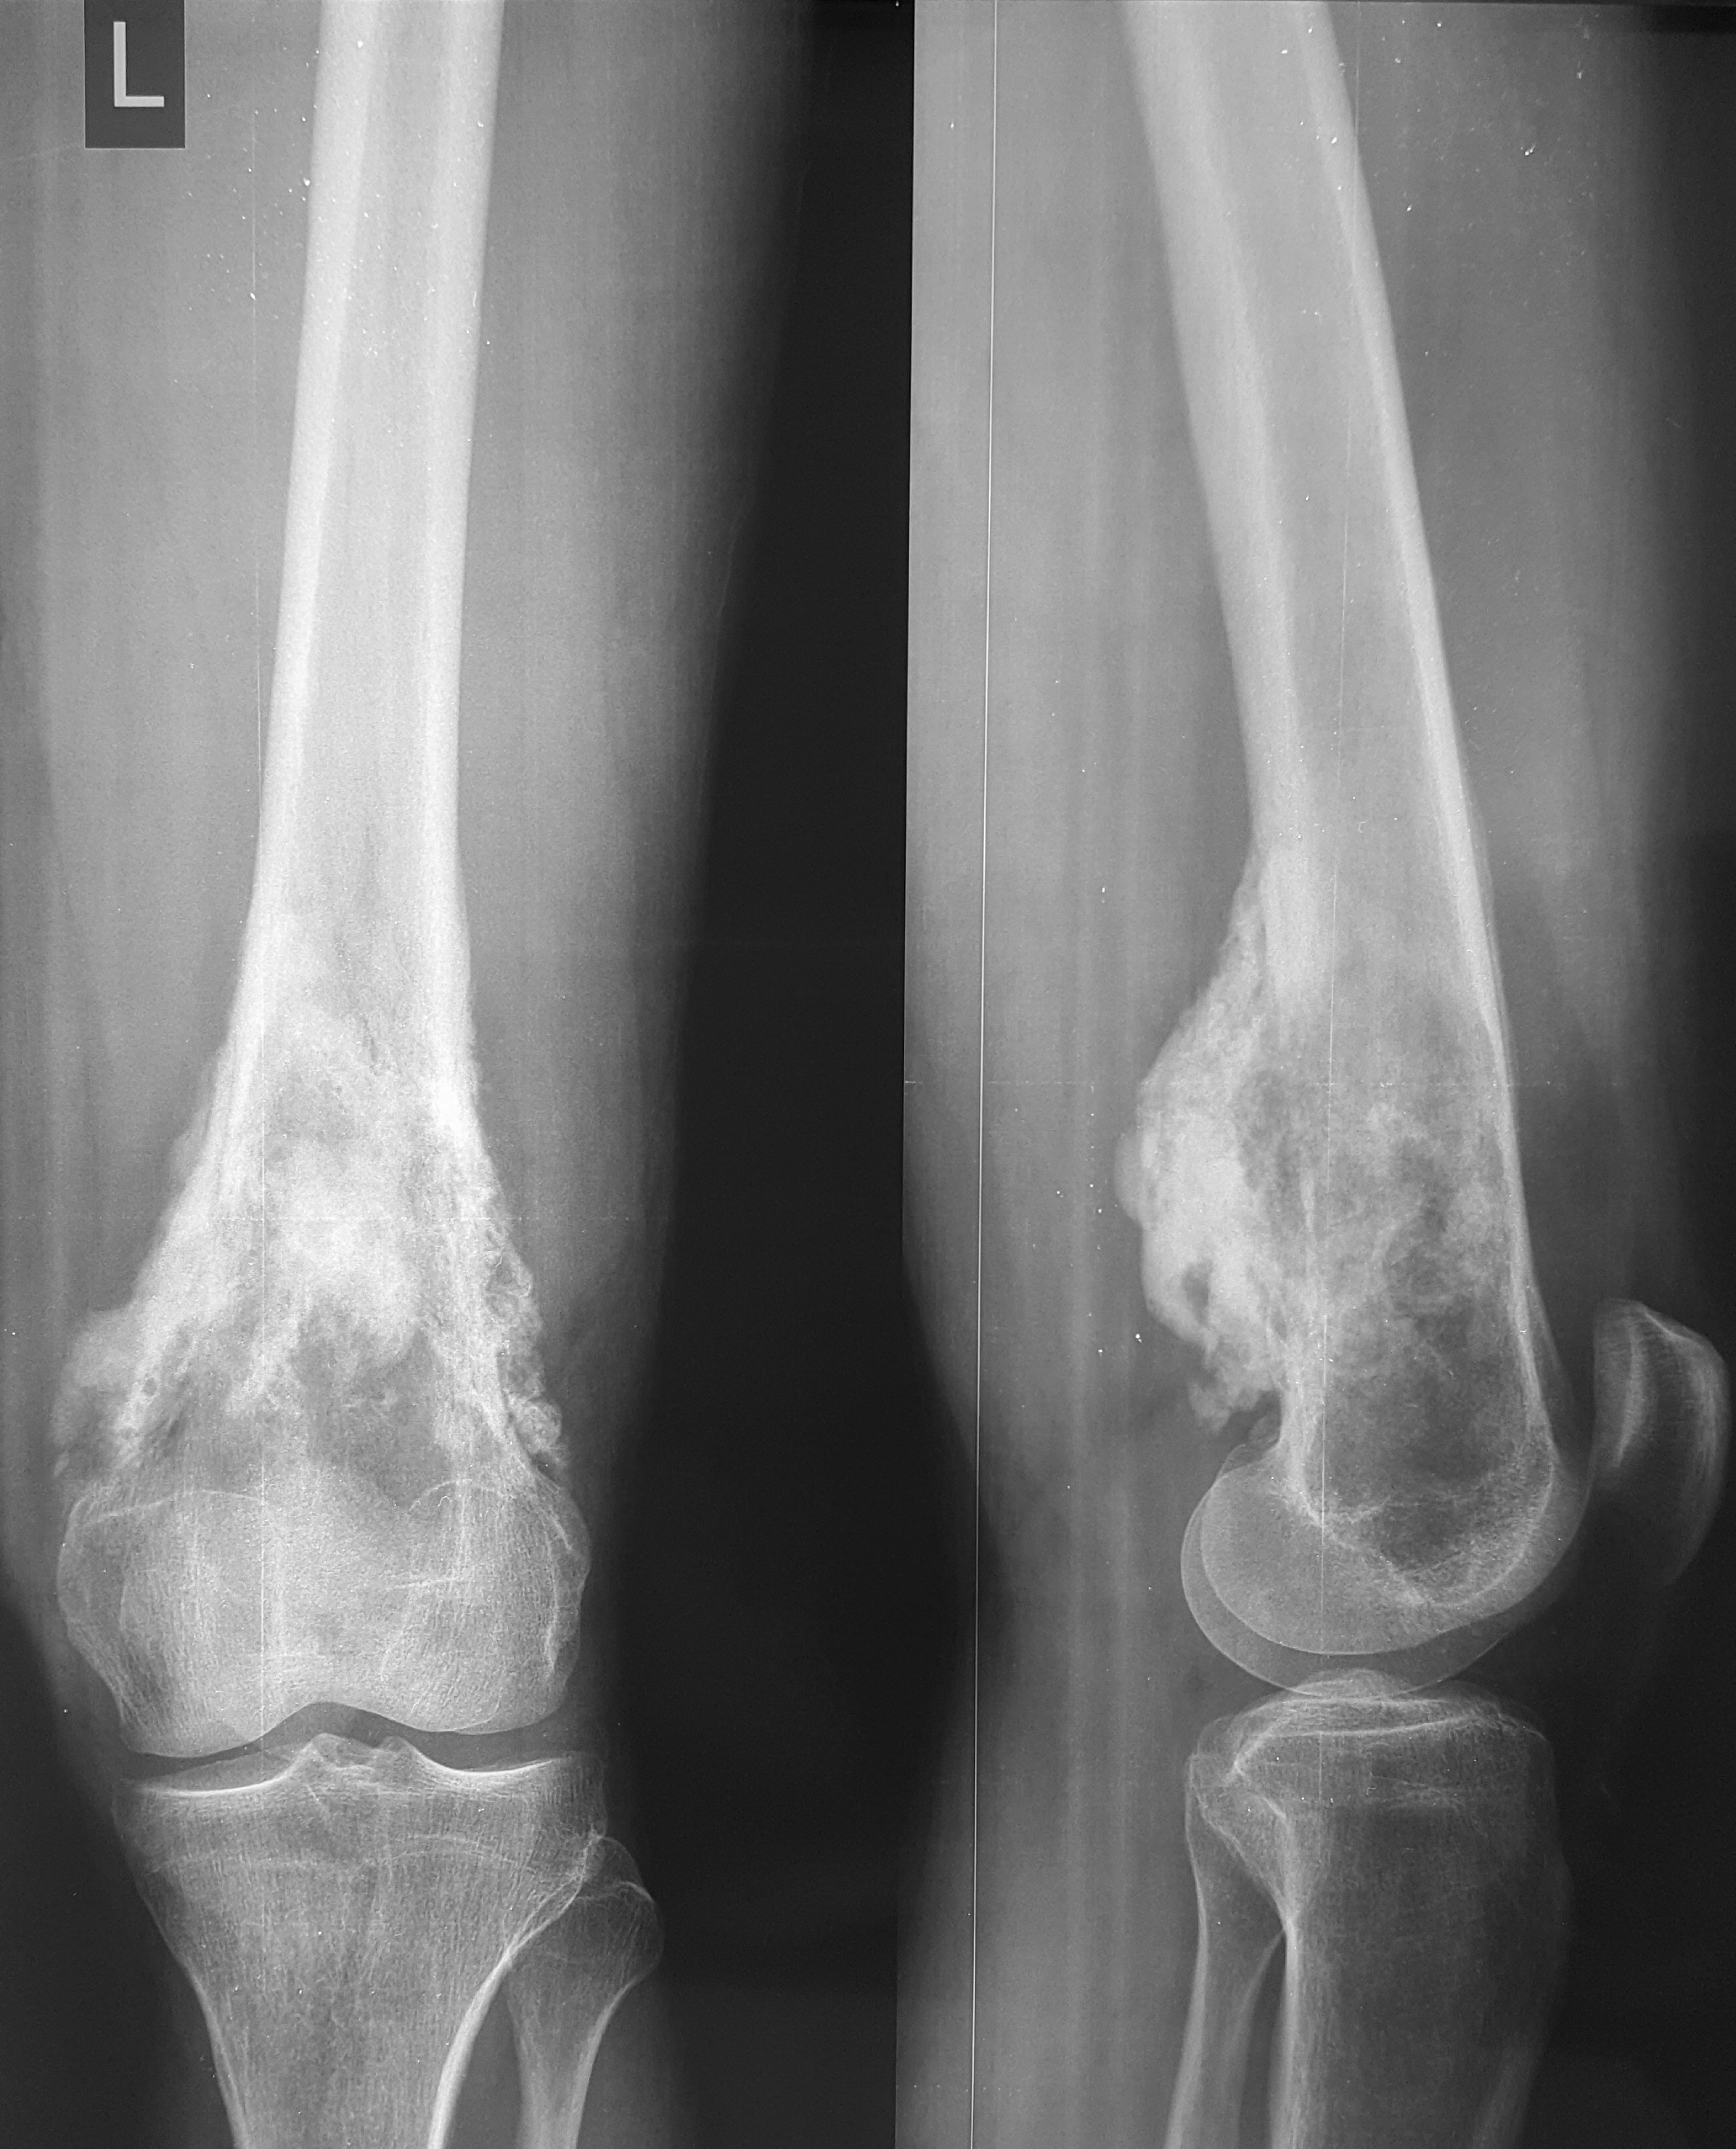

2. Բժշկական տարբեր կենտրոններում հետազոտվելուց հետո՝ 17-ամյա պատանին դիմել է «Նաիրի» ԲԿ։ Համապատասխան հետազոտություններ անցնելուց հետո՝ բուժառուի մոտ հայտնաբերվել է ոլոքի օստեոսարկոմա (ոսկրային քաղցկեղ): Նախավիրահատական բուժում ՝ քիմիոթերապիա, ստանալուց հետո՝ «Նաիրի» ԲԿ ում կատարվել է օրգանապահպան վիրահատություն : Հեռացվել են ծնկահոդն ու ոլոքի վերին երորդականը: Առաջացած դեֆորմացիան շտկել է Եվրոպայից պատվիրված էդոպրոթեզով, որը հնարավորություն է տվել պահպանել վերջույթի գործառույթը՝ քայլել, վազել և այլն։ Հետվիրահատական շրջանում բուժառուն ստացել է քիմիոթերապիա։ Այժմ գտնվում է բժիշկների հսկողության ներքո։

Վիրահատությունից առաջ

Վիրահատությունից հետո